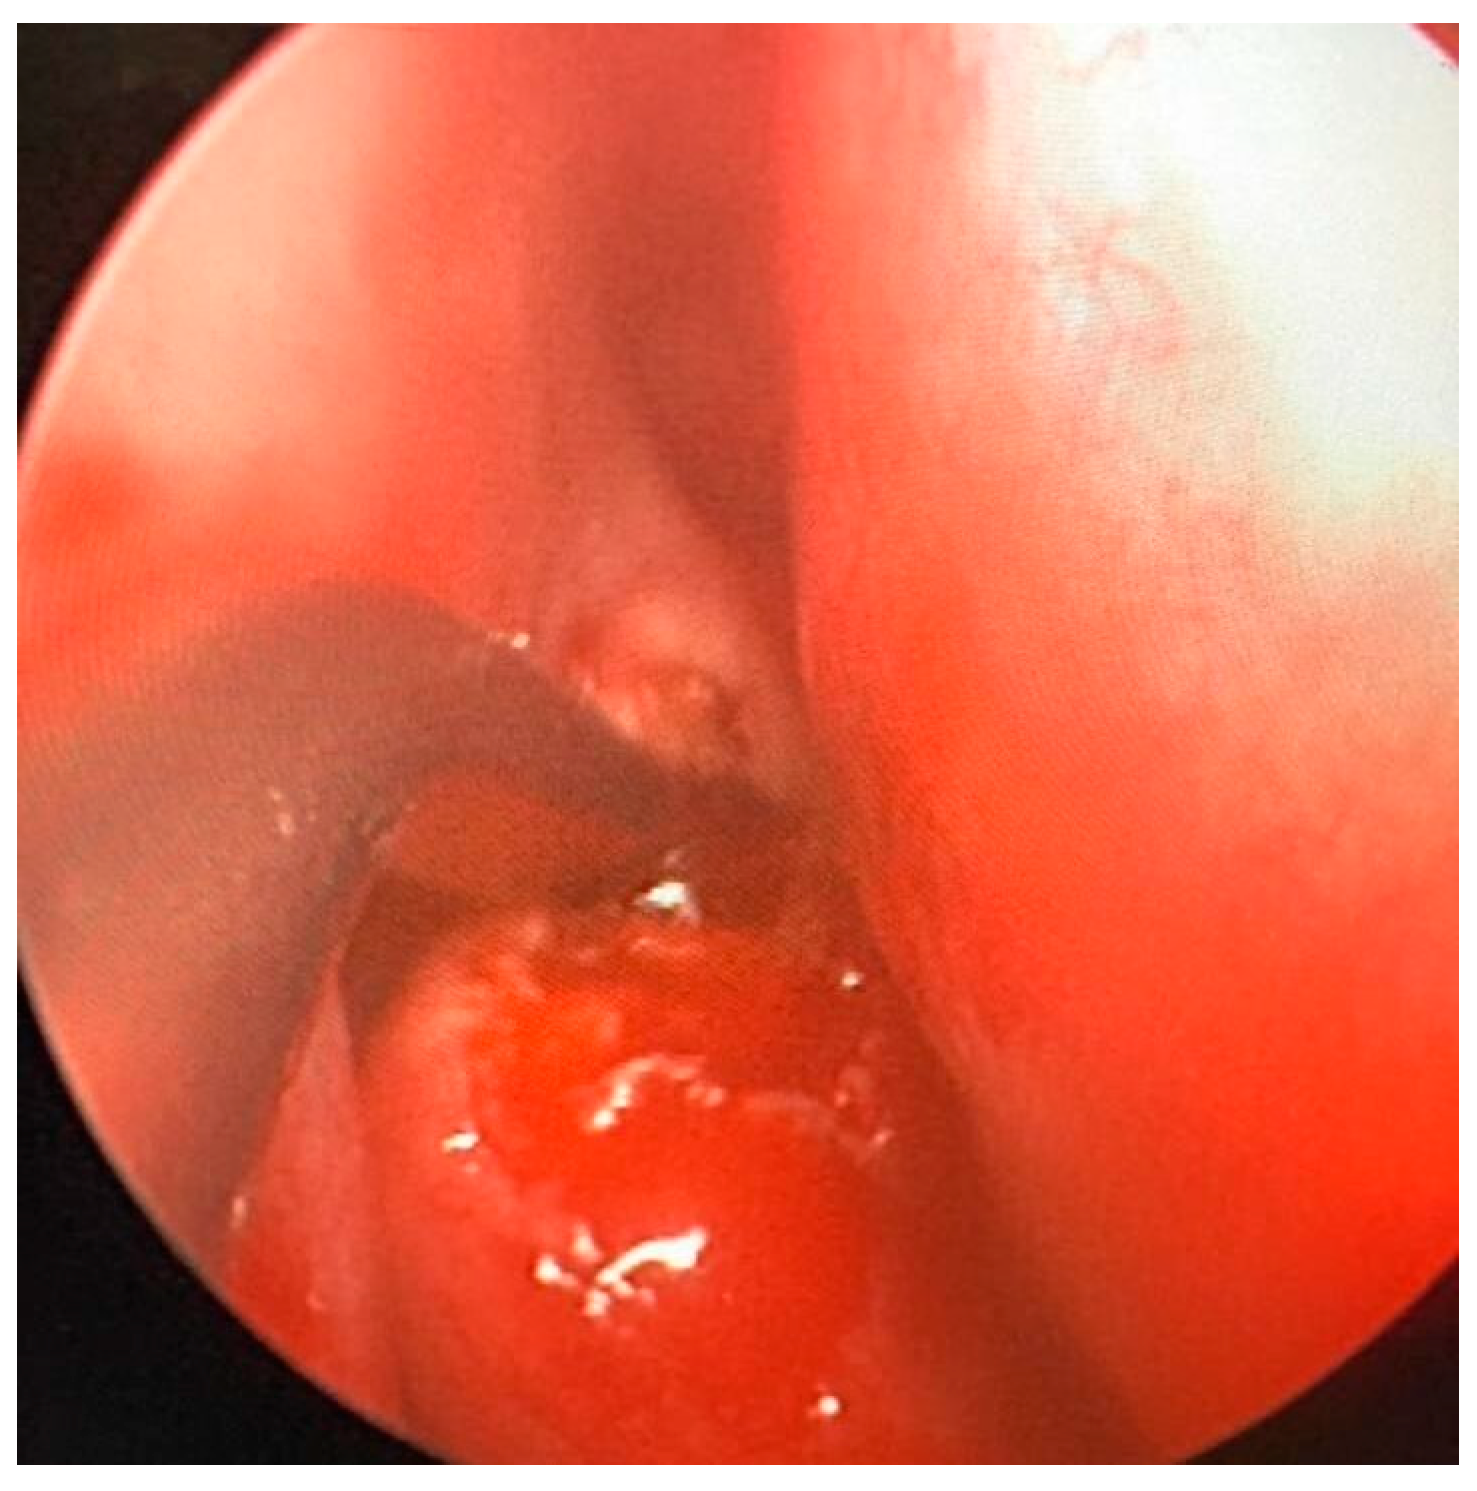

Under general anesthesia, an endoscopy of the right nasal cavity was performed, and the hypertrophy of the middle turbinate was appreciated, with a normotrophic overlying mucosa. A biopsy was attempted with Weil–Blakesley forceps, but due to the bone consistency of the lesion it was preferred to perform, through Piezo-Surgery [6] a fragmentation of the medium turbinate with a subsequent sampling of two operating samples of 15 × 25 mm and 10 × 10 mm, respectively (Figure 2).

Figure 2.

Intra-operative fragmentation of the middle turbinate. The intraoperative phase is appreciated, during which the middle turbinate was biopsied using Piezo-surgery.